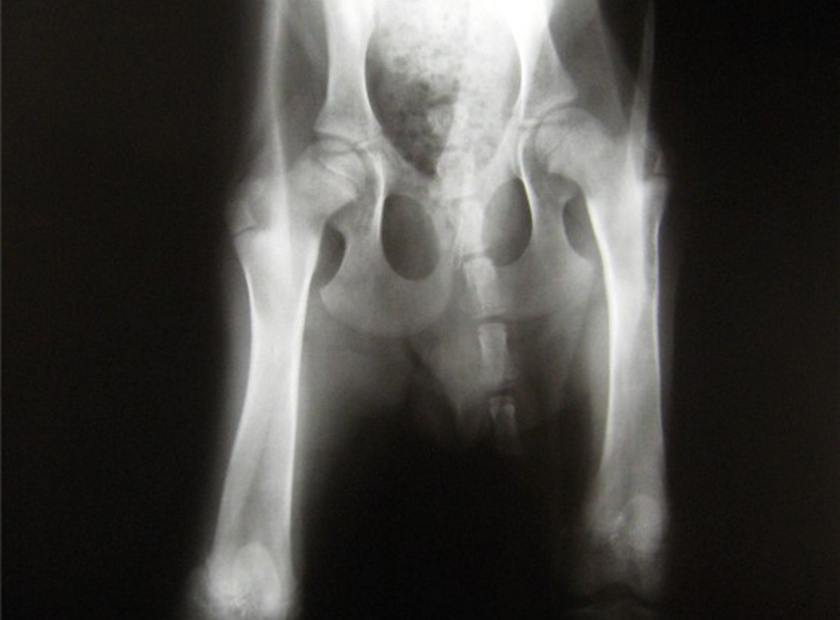

- Gelenksdyplasien wie HD, ED

Beim orthopädischen und vor allem beim Arthrosepatienten steht die Schmerzreduktion im Vordergrund. Außerdem ist es wichtig durch gezielten Muskelaufbau die betroffenen Gelenke zu stabilisieren und die verhärtete Muskulatur der anderen Gliedmaßen / des Rückens zu entlasten.